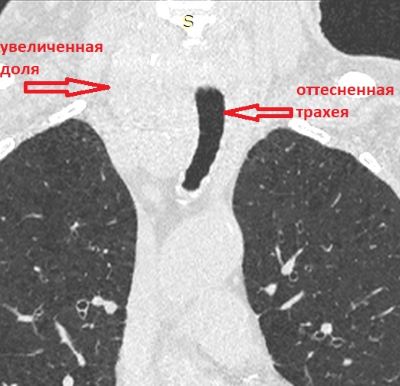

После выполнения МСКТ органов грудной полости на полученных изображениях была выявлена увеличенная правая доля щитовидной железы.

Увеличение правой доли щитовидной железы, с наличием диффузных кальцинатов в структуре.